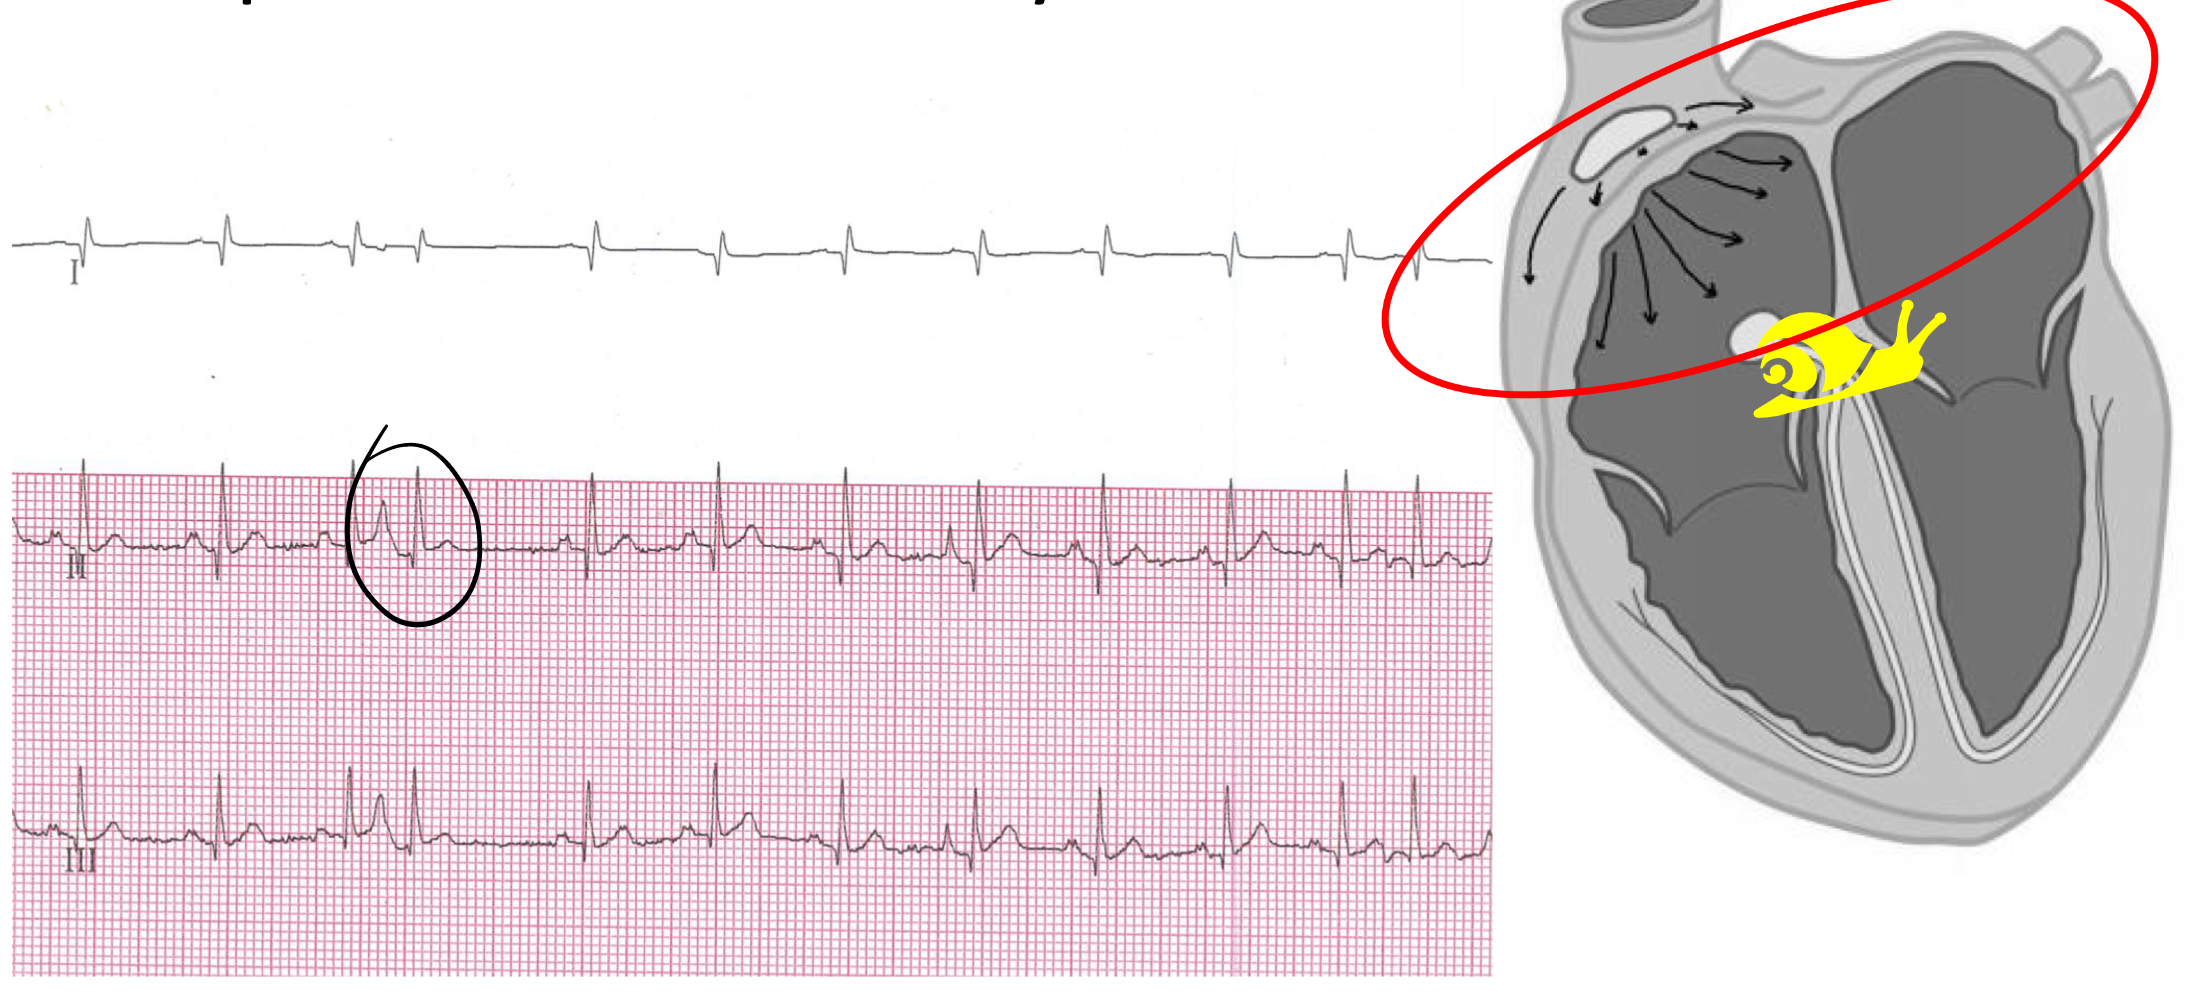

atrial fibrillation

absence of P waves

irregular rhythm

tachycardia

± f waves

narrow QRS complexes

what is the most common clinically relevant arrhythmia diagnosed in dogs?

A-fib (can be secondary to DCM, MVD)

arrhythmogenic right ventricular cardiomyopathy (ARVC)

progressive fibrofatty replacement of right, and to some degree left ventricular myocardium (seen in boxers) that manifests as right ventricle arrhythmias

arrhythmogenic right ventricular cardiomyopathy (ARVC) signs:

asymptomatic

exercise intolerance or syncope associated with ventricular arrhythmia

systolic dysfunction and CHF

arrhythmogenic right ventricular cardiomyopathy (ARVC) diagnosis:

ECG